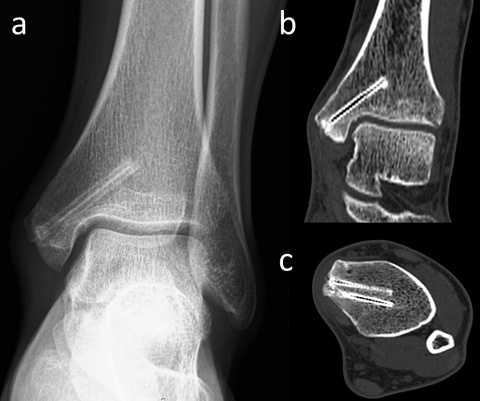

Das konventionelle Röntgenbild wird sowohl für die Diagnose als auch zur Nachbeobachtung bei der Frakturbehandlung verwendet. Häufig beurteilen Chirurgen die Knochenheilung anhand der körperlichen Untersuchung und klinischer Zeichen (wie Schmerzempfindlichkeit, Belastbarkeit und Funktionsfähigkeit) in Kombination mit den radiologischen Befunden (wie Kallusbildung, fehlender Frakturlinie und erfolgter Knochenkonsolidierung). Die radiologische Untersuchung ist also für orthopädische Chirurgen von herausragender Bedeutung [15]. Magnesiumbasierte Implantate zeigen indes ungewohnte radiographische Befunde, die durchaus zu Fehlinterpretationen führen können. Unmittelbar nach der Implantation von Magnesiumschrauben in den Knochen setzt die Degradation über einen Prozess der Korrosion ein. Die Wechselwirkung zwischen Mg und Körperflüssigkeiten führt u.a. zur Bildung von Magnesium-Hydroxid (MgOH) und H2-Gas [16]. In frühen postoperativen Röntgenaufnahmen lässt sich auch Gas im Weichgewebe beobachten, das sich in den Gewebeschichten verteilt. Klinisch produziert dieses Gas aber keine wahrnehmbare Krepitation unter der Haut oder ähnliche Symptome. Die Gasschatten im Weichgewebe bilden sich gewöhnlich rasch zurück (Abbildung 3). In frühen postoperativen Röntgenaufnahmen stellt Gas im Weichgewebe oft ein alarmierendes Signal dar, da es – bei herkömmlichen Metallimplantaten – mit gasbildenden anaeroben Infektionen in Verbindung gebracht wird. Die Bildung von Gas während der

Degradation von Mg-Implantaten hat einen vollkommen anderen Hintergrund – es handelt sich weder um eine Lockerung des Implantates noch gar um eine Infektion. Während des Abbauprozesses via Korrosion nimmt die Gasmenge zu und breitet sich im trabekulären Knochenanteil aus. Schließlich wird es jedoch vollständig resorbiert und die Mg-Schrauben zeichnen sich zunehmend prominenter ab (Abbildung 4). Tierstudien haben gezeigt, dass die Schraube schließlich durch kortikalesKnochengewebe ersetzt wird (7).

In Bezug auf die Gasbildung und Resorption zeigt die Computertomographie ähnliche Ergebnisse wie die konventionellen Röntgenaufnahmen. In der Frühphase sind sowohl die Schrauben als auch die umgebenden Gasansammlungen deutlich sichtbar (Abbildung 5). Langfristige CT-Untersuchungen zeigen, dass das Gas vollständig resorbiert wird und damit vollständig verschwindet. Die Schrauben sind bis zu ihrer Umwandlung in kortikales Knochengewebe deutlich erkennbar (Abbildung 6). Adil et al. haben nachgewiesen, dass diese Konturen vier Jahre nach der Implantation in der tomographischen Dichtemessung ähnliche Hounsfield-Einheiten aufweisen wie die umgebende Kortikalis (17). Darüber hinaus erzeugen Implantate auf Magnesiumbasis – im Gegensatz zu konventionellen Metallimplantaten wie Titanschrauben – nur minimale Metallartefakte (18-20). Für die Nachbeobachtung der Patienten stellt dies einen signifikanten Vorteil dar.

Magnesiumschrauben fixiert wurde. (a) In der anterior-posterioren

Röntgenaufnahme des Knöchels in Monat 30 nach der Operation sind

die Heilung der Fraktur und die Umrisse der Schrauben sichtbar. (b)

Koronare und (c) axiale CT-Aufnahmen weisen keine Gasansammlung

im Knochen auf und die Schrauben zeigen eine ähnliche Dichte wie die

umgebende Kortikalis.